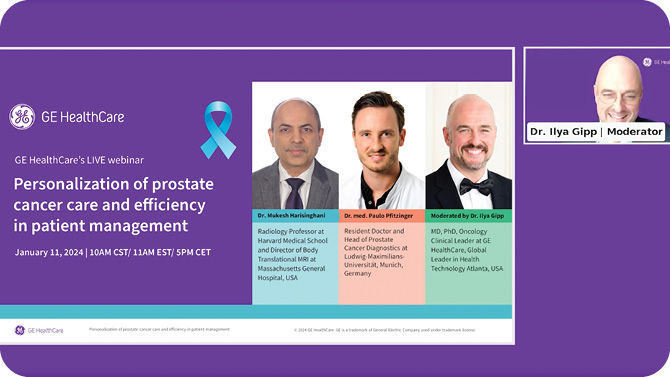

Where cancer and care connect.GE HealthCare unites cancer screening with precision image guided therapy through an eco-system of devices and digital solutions powered by AI to create seamless coordination and advance the patient journey throughout the entire pathway from early detection to follow up and assessment.Our collaborations, solutions and expertise drive optimization and transform personalized cancer care for improved outcomes.